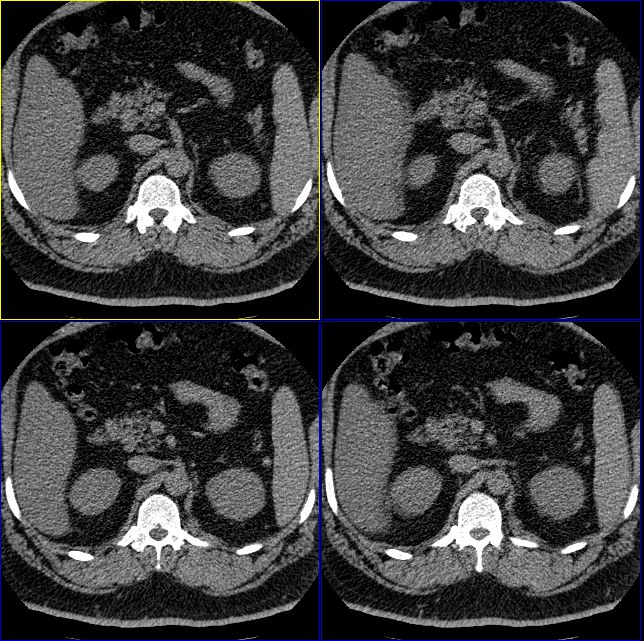

男性,37岁。体型极度肥胖,达300余斤。

标题: 双侧肾上腺没有问题么?

怎么回事啊,难道肾上腺没有问题么?右侧肾上腺有明显的脂肪性类圆形肿物,左侧也觉得有增生性改变。我们诊断为右肾上腺髓样脂肪瘤,左侧肾上腺增生。大家再仔细看看。

肾上腺很可能有问题,建议矢状位重建,另外结合肾上腺内分泌测定。左侧增生不能除外。

右侧肾上腺好像有一个类圆形的囊性包块,内部密度象是脂肪

1.肾上腺区囊性占位

2.脂肪肝

只能考虑有脂肪肝,至于右侧肾上腺“病变”会不会就是内外支间的脂肪组织?